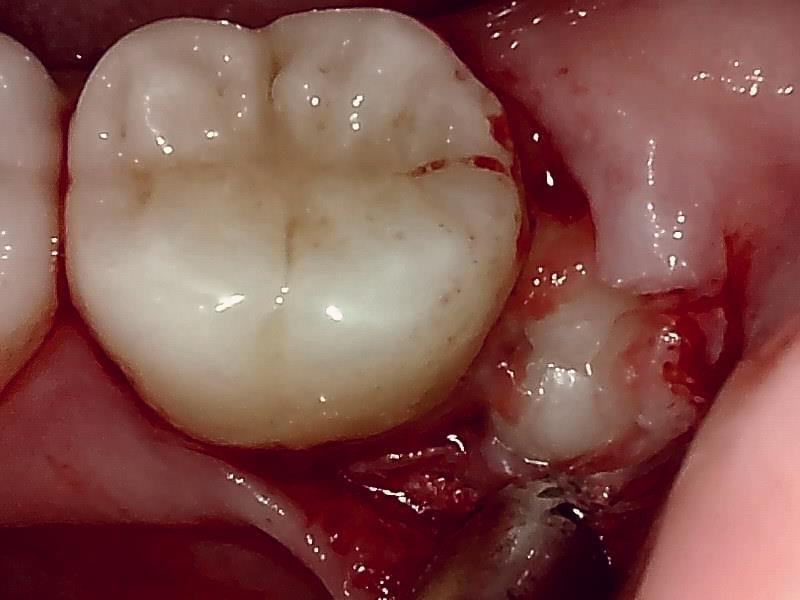

部位:左下8番埋伏歯

切開 歯肉剝離

歯肉を切開し、歯が見えるようにして、

周辺の骨を削らないように親知らずを分割し抜きやすくしていきます。

この抜歯法により術後の腫れ痛みが大幅に軽減されます。